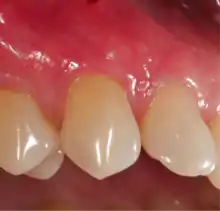

Gingival grafting, also called gum grafting or periodontal plastic surgery,[1][2][3] is a generic term for the performance of any of a number of periodontal surgical procedures in which the gum tissue is grafted. The aim may be to cover exposed root surfaces or merely to augment the band of keratinized tissue.

Exposure of the tooth root due to loss of keratinized tissue around the neck of a tooth is referred to as gingival recession. This can result in sensitivity or pain from the exposed tooth root surface (dentin is more permeable and soft compared to enamel and dentin is what makes up the tooth root).[7] Recession may also cause an unasthetic appearance especially if located in the anterior dentition (front teeth). While not all cases of gingival recession require surgical correction, there are various options if that is what the patient desires.[8] It should be reinforced that recession left untreated will not result in tooth loss, contrary to popular belief. Also, recession that is left untreated can be maintained and the inflammation kept at bay with proper brushing and oral hygiene technique.[5] On the other hand, if one desires to pursue corrective therapy, there are a wide variety of techniques ranging from autograft (your own tissue, usually taken from the palate), allograft (someone else's tissue, cadaver), xenograft (animal, usually porcine or bovine) or simply repositioning of the tissue native to the site.[9] The benefits of corrective therapy often result in decreased sensitivity through coverage of the root surface in addition to a gain in the keratinized tissue mentioned beforehand.